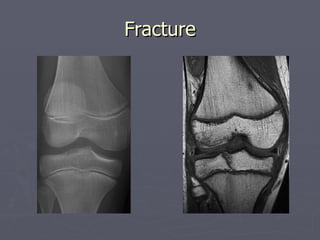

Fracture

Indications Occult fracturesMarrow abnormality Ligament pathologies Tendon pathologies Muscular injuries Infection Bone and soft tissue tumour Labral pathologies